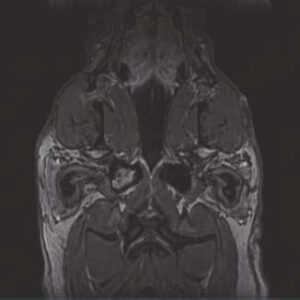

- Image Quality comparable to 1.5T MRI in the market

The PANION PRO comes with the double-pole open magnet design with a wide opening gap of 40 cm to accommodate large-sized animals on an efficient patient handling platform, the strongest gradient amplitude at 33mT/m and slew rate of 90 T/m/s, among all other open MRI systems, resulting in high spatial resolution of images in short scan time. The 6-direction patient table permits iso-centre imaging of all anatomical regions.

Clinical Images